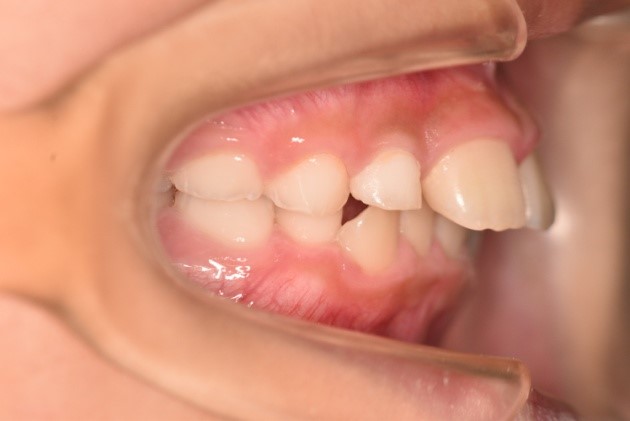

こちらは、お口の中を横から見たときの写真です。

の方に比べ、の方は上の歯がでているのが、見てわかると思います。